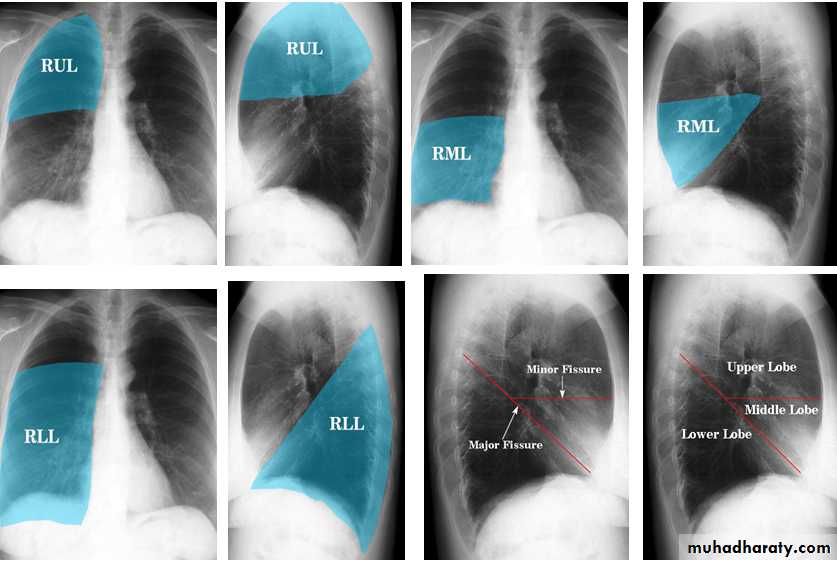

Lung

The left lung has two lobes and the right has three

Each lobe has its own pleural covering

The horizontal fissure (right) is often seen on a normal frontal view

The oblique fissures are often seen on a normal lateral view .

Lobes and fissures

This cut-out of a lateral chest x-ray shows the positions of the lobes of the right lung

On the left the oblique fissure is in a similar position but there is usually no horizontal fissure, and so there are only two lobes on the left.

Radiologic anatomy of the RT lung lobes

Radiologic anatomy of the LT lung lobes